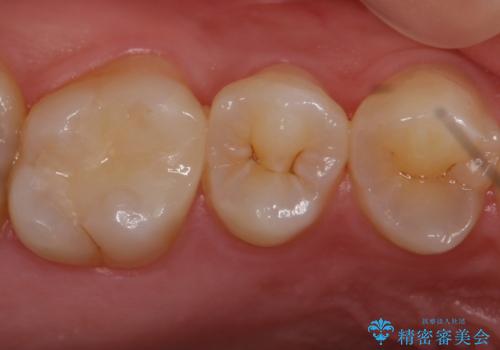

歯と歯の間の虫歯 セラミックインレーでの治療

歯と歯の間に虫歯があったためセラミックインレーで治療をしていきました。

歯と歯の間は虫歯の好発部位となっています。

今後の虫歯リスクを抑えるためにも適合の良い補綴物を装着することは有効です。